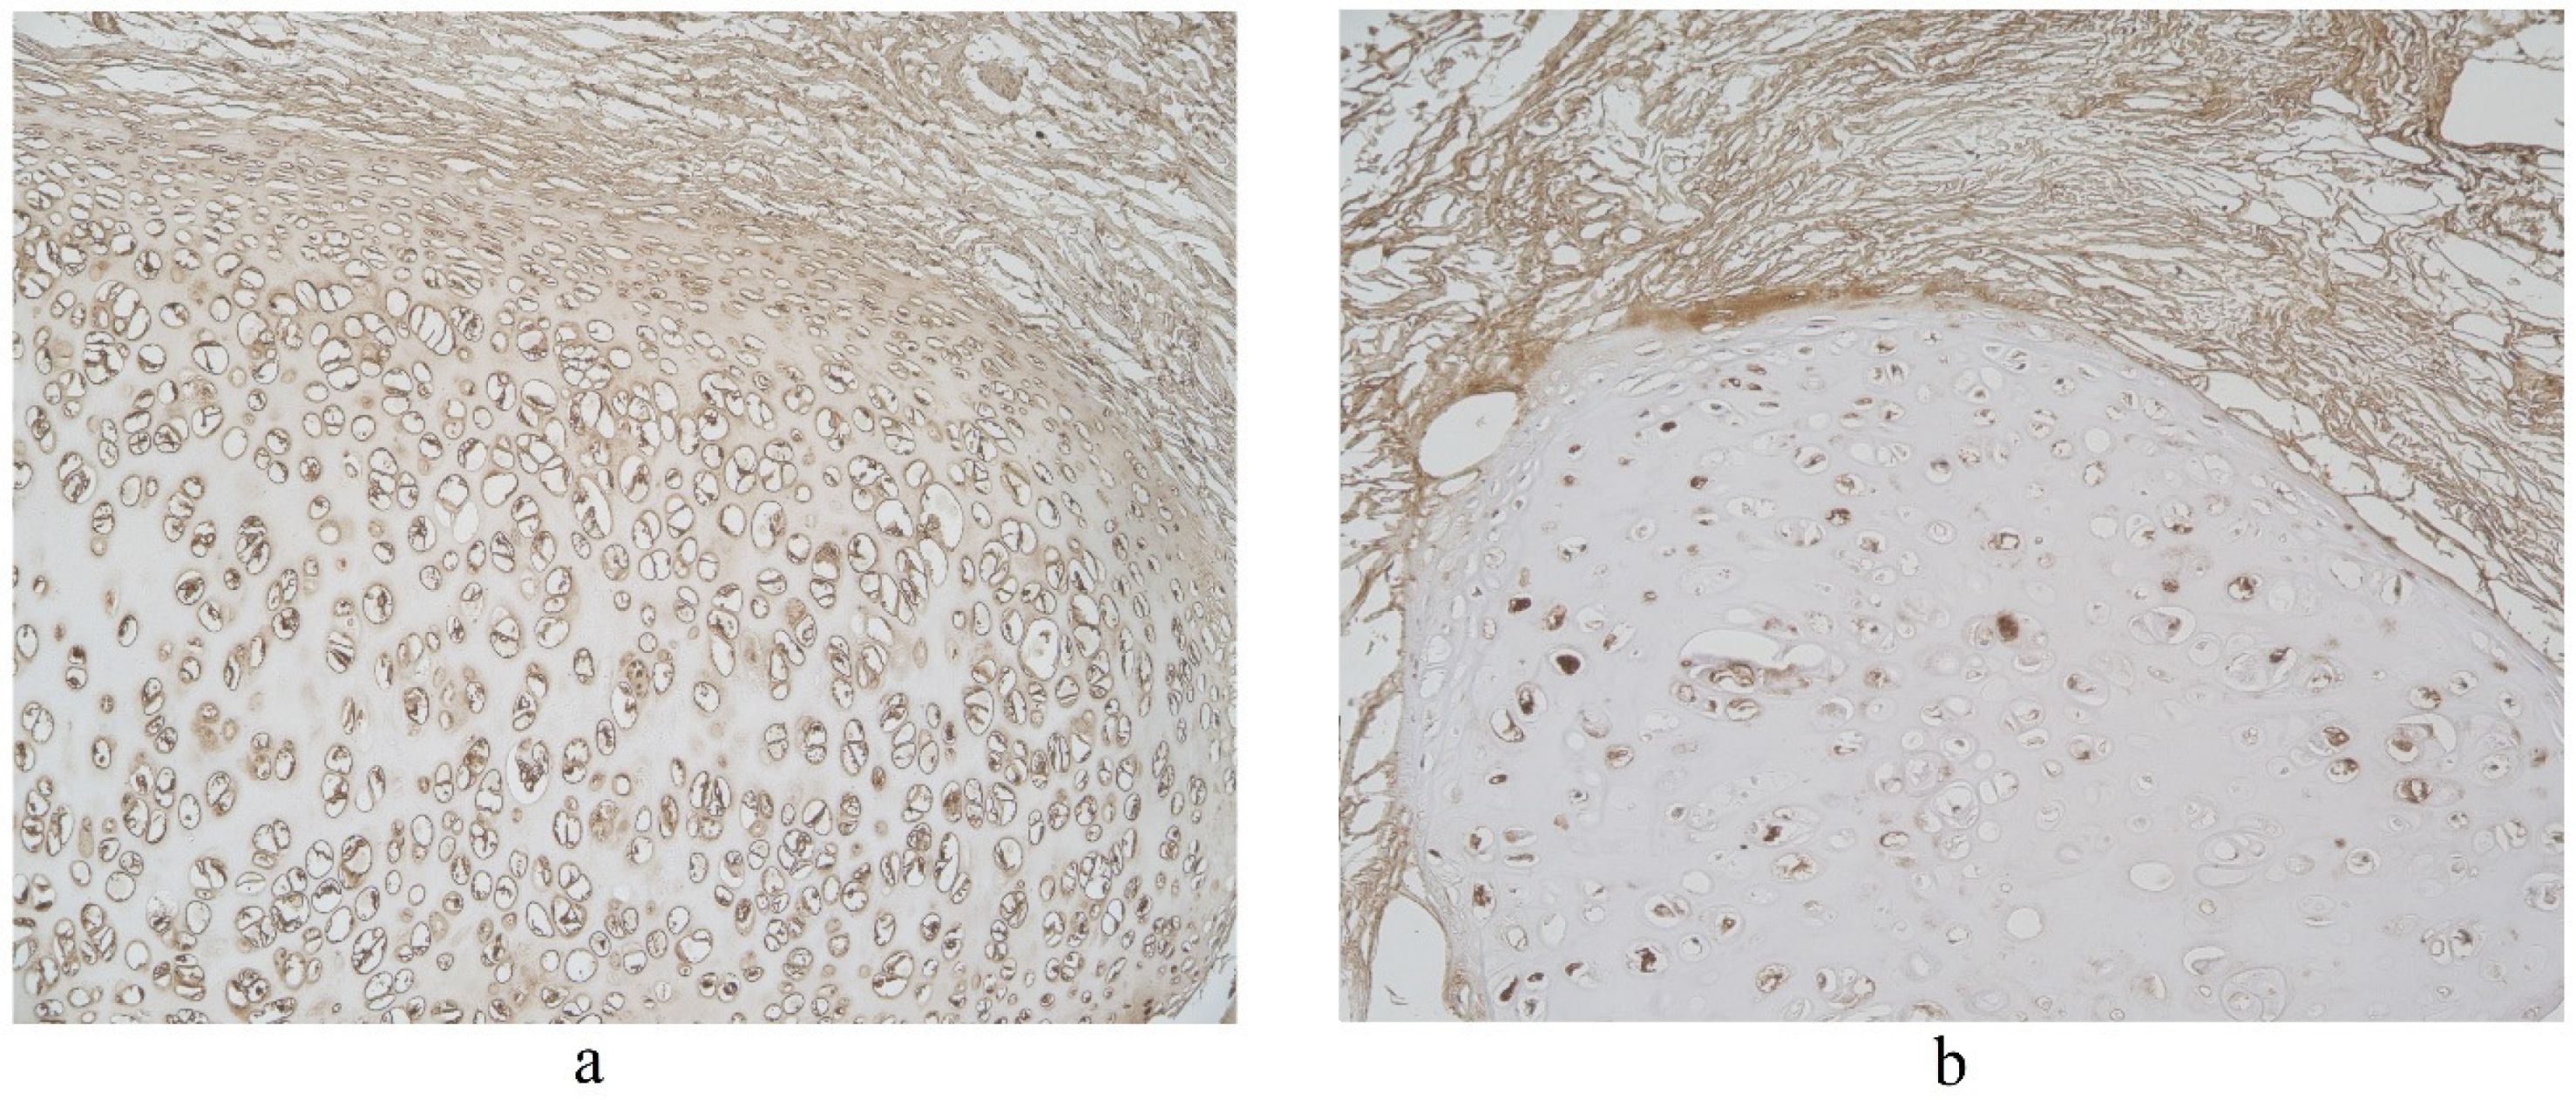

3.1. Tissue Review

3.2. Immunohistochemical (IMH) Data